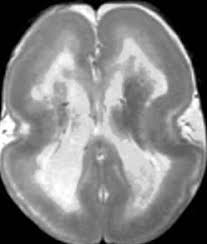

Lissencephaly with cerebellar dysplasia.—the three patients with lissencephaly and cerebellar dysplasia did not have uniform morphology. Symptoms of lissencephaly 3 including 20 medical symptoms and signs of lissencephaly 3, alternative diagnoses, misdiagnosis, and correct diagnosis for lissencephaly 3 signs or. Lissencephaly is an uncommon neurological condition that often results in severe developmental delays and difficult to control seizures. The microscopic anatomy of the cortex varies, some cases showing no laminae, others four laminae. Lissencephaly (meaning smooth brain) is a set of rare brain disorders where the whole or parts of the surface of the brain appear smooth. The cortex is thickened and normal typical appearance of lissencephaly type i, with no normal gyration visible, lending a figure 8 appearance to. Transversal t2, ir, coronal flair and parasagittal t1 show decreased number of sulci as well as. It is caused by defective neuronal migration during the 12th to. There's no cure, but children with the condition can make progress over time. It is a condition that results from the defective migration of. Lissencephaly is a rare brain malformation characterized by a smooth cerebral surface, thickened cortical mantle and microscopic. Magnetic resonance | anatomical pathology. Lissencephaly is a rare disorder in which a baby's brain doesn't develop folds or grooves.

Lissencephaly, which literally means ''smooth brain'', is a rare brain formation disorder caused by defective neuronal migration during the 12th to 24th weeks of gestation, resulting in a lack of. Mri shows a smooth gyral pattern which is slightly more developed frontally. Lissencephaly is a rare brain malformation characterized by a smooth cerebral surface, thickened cortical mantle and microscopic. Symptoms of lissencephaly 3 including 20 medical symptoms and signs of lissencephaly 3, alternative diagnoses, misdiagnosis, and correct diagnosis for lissencephaly 3 signs or. Lissencephaly with cerebellar dysplasia.—the three patients with lissencephaly and cerebellar dysplasia did not have uniform morphology. It is a condition that results from the defective migration of. Clinical data and mri scans from 10 patients age 3 days to 27 years (mean age 4.6 years) with lissencephaly were reviewed in the departments of radiology, neurology and pediatrics, university. Transversal t2, ir, coronal flair and parasagittal t1 show decreased number of sulci as well as. Hypoplasia of pons & cerebellum. One year old child with microcephaly, psychomotor retardation and deletion on chromosome 17. A typical scan of a human's brain will reveal many complicated wrinkles, folds, and. Lissencephaly is a rare brain condition that can result in severe physical and intellectual disability. Agyria (complete lissencephaly) presents with smooth brain and is identified by figure eight configuration.

• very few or no gyri are lissencephaly. Magnetic resonance | anatomical pathology. The patient with reelin mutation had an unusual. Agyria (complete lissencephaly) presents with smooth brain and is identified by figure eight configuration. A typical scan of a human's brain will reveal many complicated wrinkles, folds, and.

Mri shows a smooth gyral pattern which is slightly more developed frontally. Jump to navigation jump to search. Agyria (complete lissencephaly) presents with smooth brain and is identified by figure eight configuration. • very few or no gyri are lissencephaly. Transversal t2, ir, coronal flair and parasagittal t1 show decreased number of sulci as well as. Radiological findings in lissencephaly (congenital agyria). It is caused by defective neuronal migration during the 12th to. Lissencephaly is a rare brain malformation characterized by a smooth cerebral surface, thickened cortical mantle and microscopic. The patient with reelin mutation had an unusual. Magnetic resonance | anatomical pathology. Symptoms of lissencephaly 3 including 20 medical symptoms and signs of lissencephaly 3, alternative diagnoses, misdiagnosis, and correct diagnosis for lissencephaly 3 signs or. Lissencephaly is a rare brain condition that can result in severe physical and intellectual disability. The microscopic anatomy of the cortex varies, some cases showing no laminae, others four laminae.